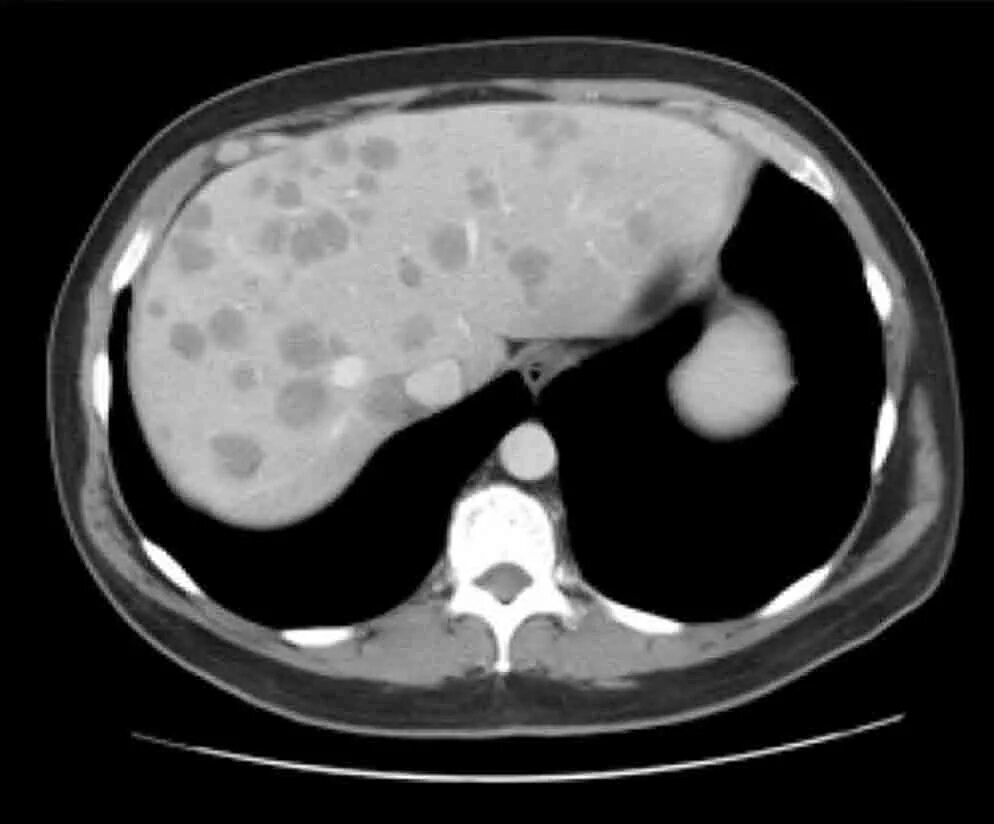

Ошибки кт